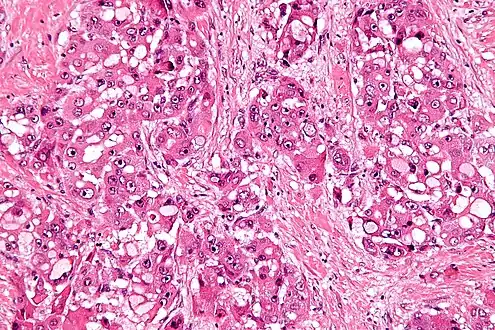

Micrograph of fibrolamellar hepatocarcinoma showing the characteristic laminated fibrosis between the tumor cells with a low NC ratio. H&E stain.

The histopathology of FHCC is characterized by laminated fibrous layers, interspersed between the tumor cells. Cytologically, the tumor cells have a low nuclear to cytoplasmic ratio with abundant eosinophilic cytoplasm. Tumors are non-encapsulated, but well circumscribed, when compared to conventional HCC (which typically has an invasive border).